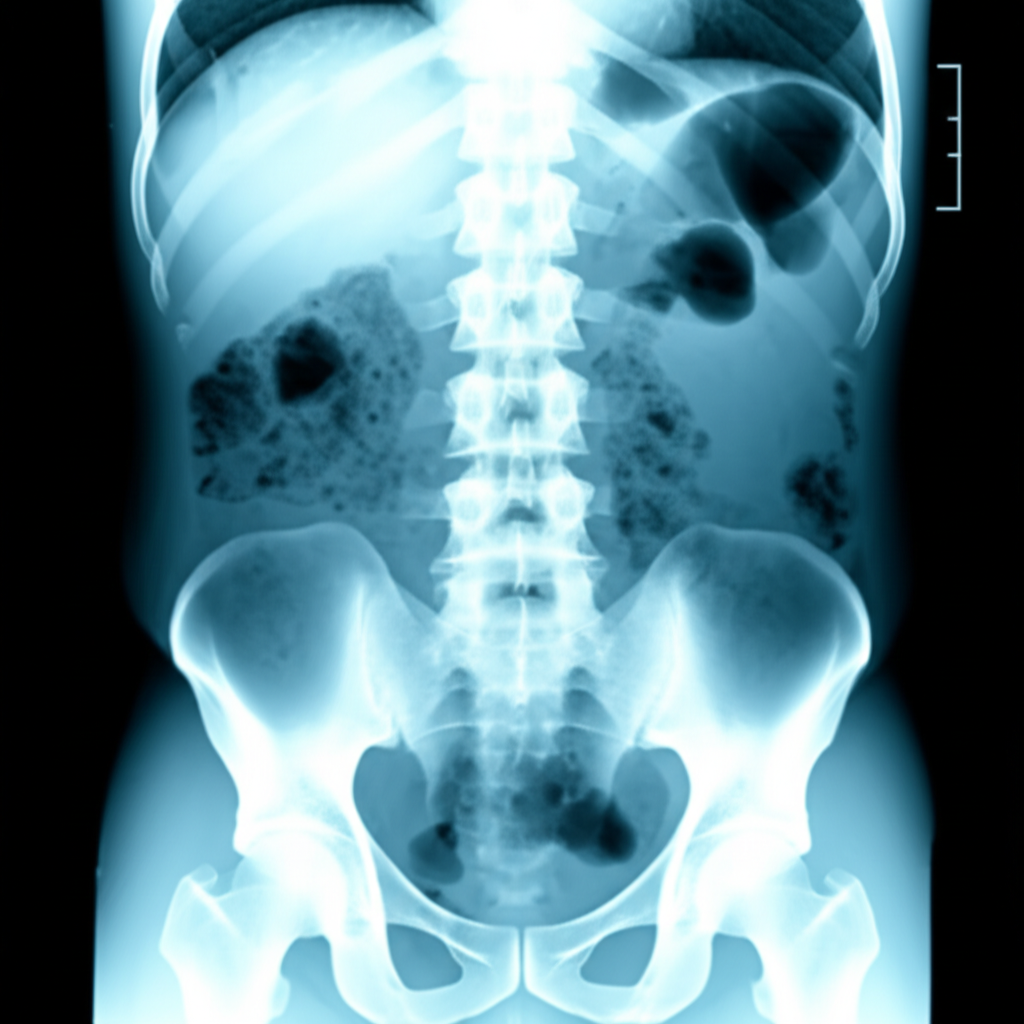

4. 복부 X-ray

복부 X-ray를 통해 신장 결석, 장폐색 등을 확인할 수 있습니다. 그러나, 작은 결석이나 연조직 질환은 잘 보이지 않을 수 있습니다.